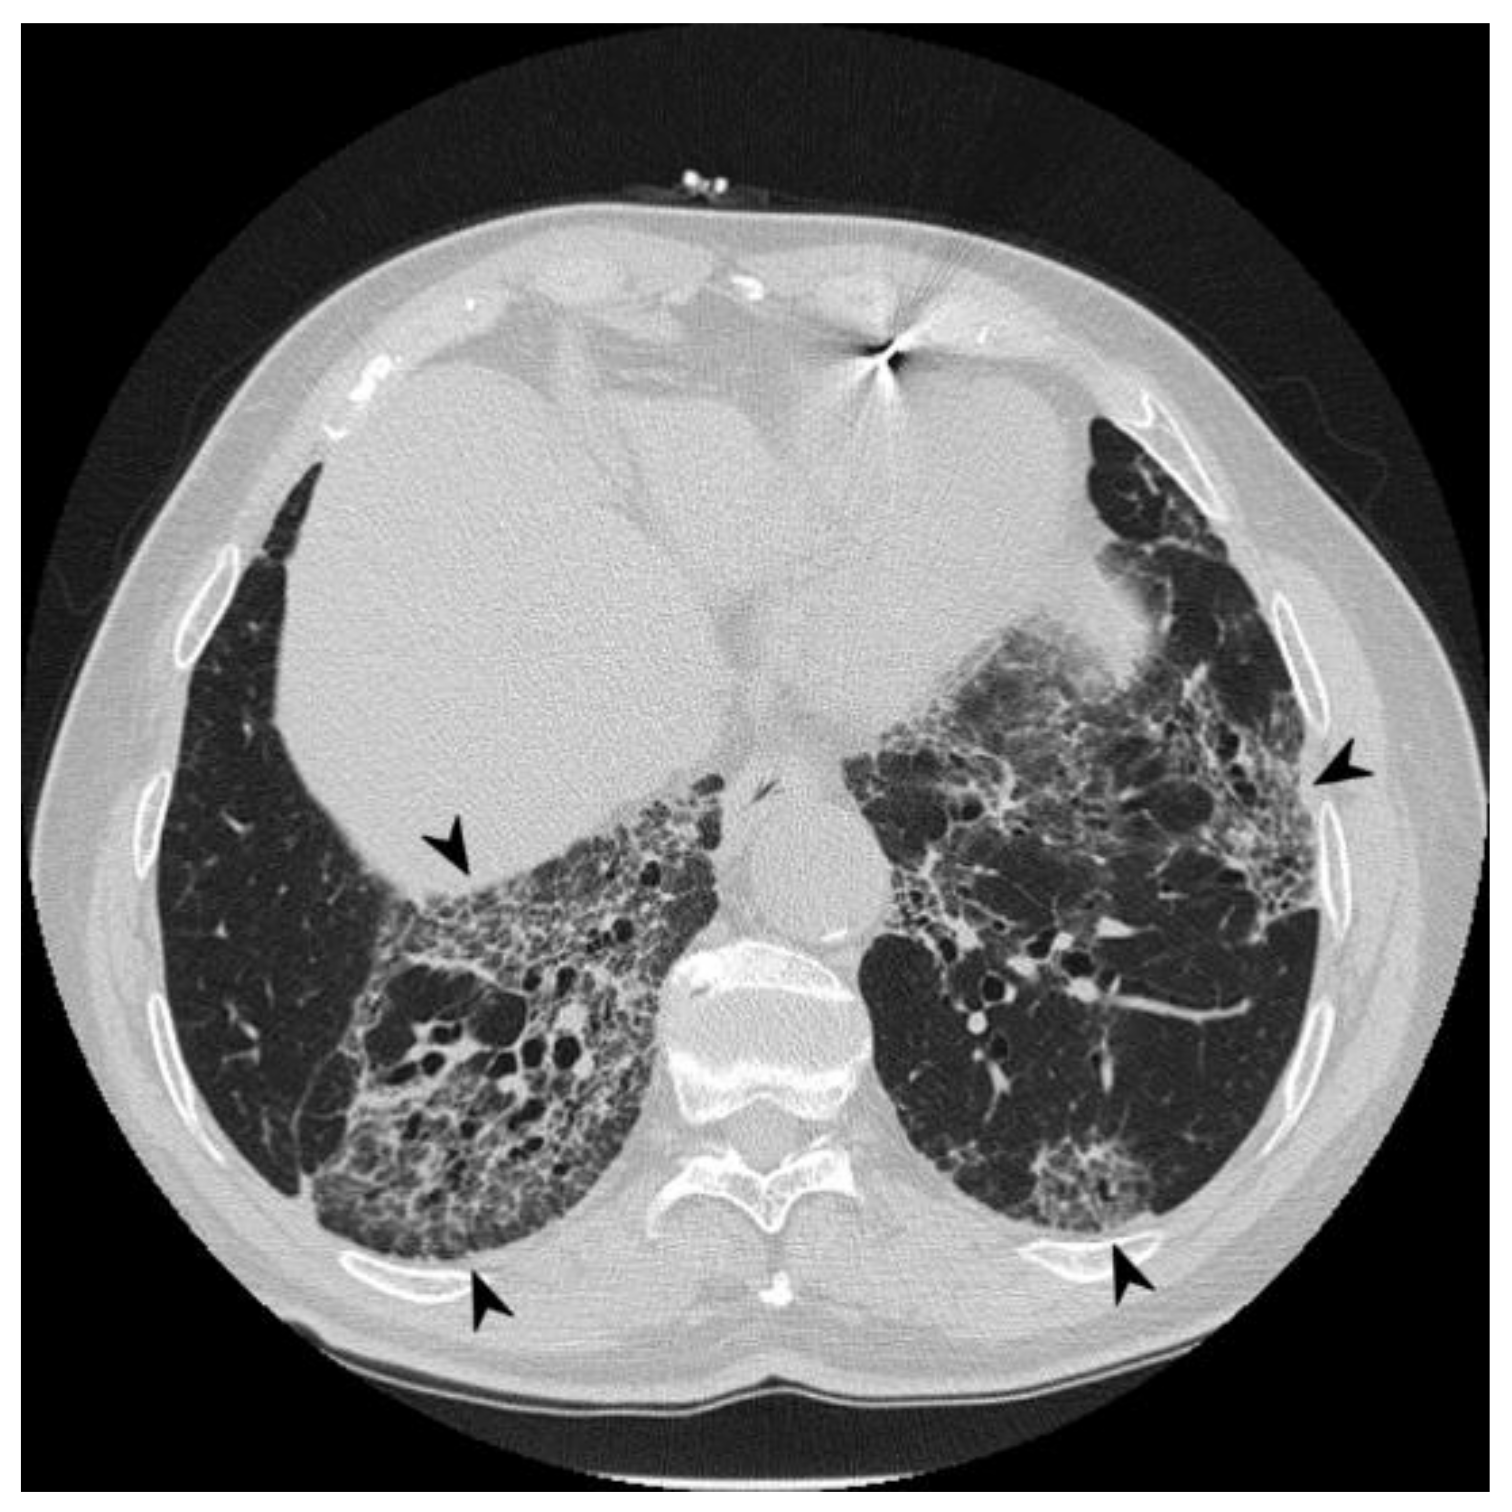

| HRCT Pattern | Associated Drugs |

|---|---|

| Fibrotic pattern | Nitrofurantoin (chronic toxicity), methotrexate, sulfalazina, rituximab, tocilizumab, bleomycin, busulfan, cyclophosphamide (chronic toxicity), amiodarone (form with fibrous course), tocainide, cocaine |

| Organizing pneumonia | Nitrofurantoin (chronic toxicity), methotrexate |

| Mosaic pattern | Nitrofurantoin (acute toxicity), methotrexate, sulfalazina |

| Isolated ground glass | Rituximab, tocilizumab, cyclophosphamide (acute reaction), amiodarone (initial stage), cocaine |

| Alveolar hemorrhage | Penicillamine, rituximab, cocaine |

| Pulmonary edema | Acetyl-salicylic acid, mitomycin |

| Pleural effusion | Sulfonamides, methotrexate |